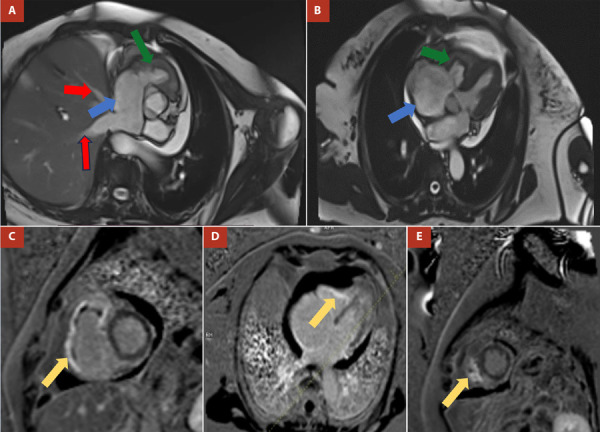

心内膜肌纤维化或戴维斯病是一种罕见的限制性心肌病的原因。它的特点是纤维物质沉积在心内膜,导致快速进行性心力衰竭。它最常影响两个心室,孤立地累及右心室是最不常见的形式。该疾病的临床表现以右心衰症状为基础,但也可能出现心律失常和传导障碍。治疗是由充血的管理和有症状患者的手术干预决定的。我们提出了第一例分离自哥伦比亚右心室的心内膜肌纤维化,我们描述了临床,病因学,影像学和管理特点,以便向医学界提供对这种疾病的大致理解,重点是一种不寻常的表现方式。

Endomyocardial fibrosis or Davies disease is a rare cause of restrictive cardiomyopathy. It is characterized by the deposit of fibrous material in the endocardium that leads to quickly progressive heart failure. It most frequently affects both ventricles, with isolated involvement of the right ventricle being the least common form. The clinical presentation of this entity is based on symptoms of right heart failure, although arrhythmias and conduction disorders may also be present. The treatment is determined by the management of congestion and surgical intervention in symptomatic patients. We present the first case of endomyocardial fibrosis isolated from the right ventricle in Colombia, we describe the clinical, etiological, imaging and management characteristics in order to deliver to the medical community an approximate understanding of this disease focusing on an unusual way of presentation.